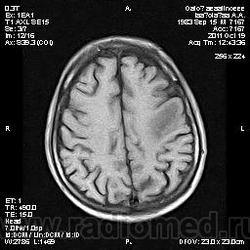

Молодой человек, жалуется только на головные боли и слабость в правой руке и ноге (около месяца).

Пациент полуасоциальный, нельзя исключить анамнез наркоманский....

ППН (включая ячейки пирамидок и сосцевидные отростки) тотально заполнены жидкостным компонентом...

Колеги, спасибо за высказывания. В данном случае про наркоманский анамнез указано не спроста... Есть мнение, что в этом лежит точка отсчета.... По поводу абсцесса и гематомы - не согласен; по поводу первого - нет соответствющей клиники, по поводу второго - не характерна локализация и сигнальные характеристики. Не буду томить общественность касательно собственного мнения. Есть две гипотезы, о которых думается в данном случае: прогрессирующая лейкоэнцефалопатия и новообразование... Но без контраста их не разрешить...